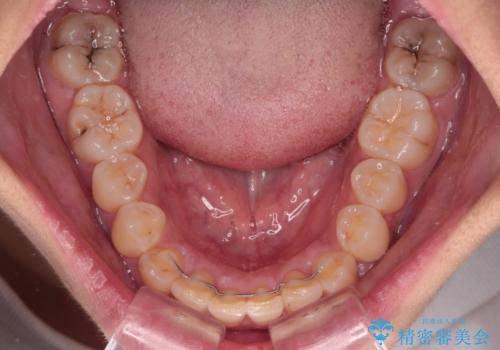

前歯のデコボコと隠れてしまう下顎前歯 インビザラインですっきりと改善

インビザライン発注後に長期滞在先から2年間ほど帰国することができず、インビザラインの有効期限内に終了できるのか不安でしたが、矯正治療開始後は十分な装着時間を達成され、1年未満の期間で無事に終えることができました。